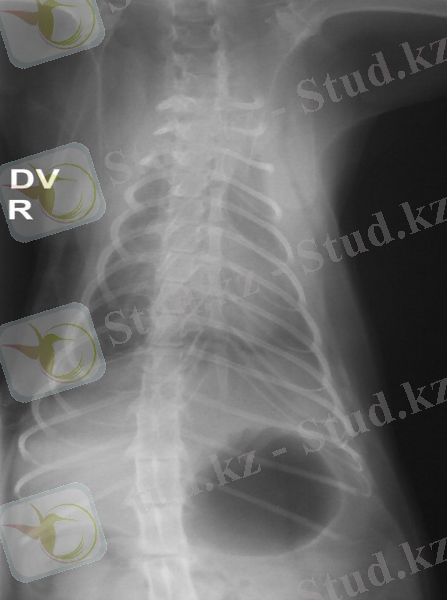

- Рентгенография

- Спондилоэктомия